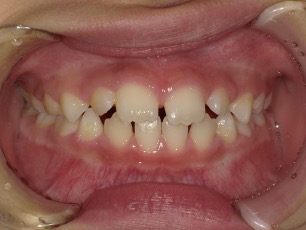

| 年齢・性別 | 男性 |

|---|---|

| 主訴 | 歯の隙間が気になる |

| 治療期間・回数 | 14ヶ月 |

| 費用 | 330,000円(税込) |